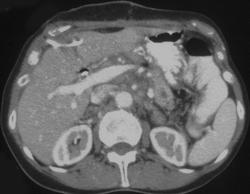

Chronic Pancreatitis